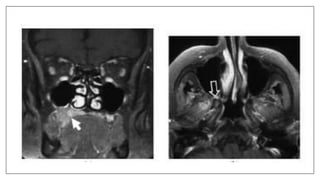

Metal artifacts: Braces

Braces may cause an artifact distant from the source. The axial proton density

and T2-weighted images exhibit horseshoe shaped artifacts. Note it is much

subtler on the T2 image.

Metal Artifact Causing Cone head Appearance

presence of a small metal clip on an elastic in the patients hair. Ferrous metal will cause a

magnetic field inhomogeneity which in turn causes a local signal void, often ringed by an

area of high signal intensity, as well as a distortion of the image. Once the metal was

removed the patients head returned to a more normal shape.

Patient Wearing Belt

The patient was wearing a metal-studded belt during this coronal T1-